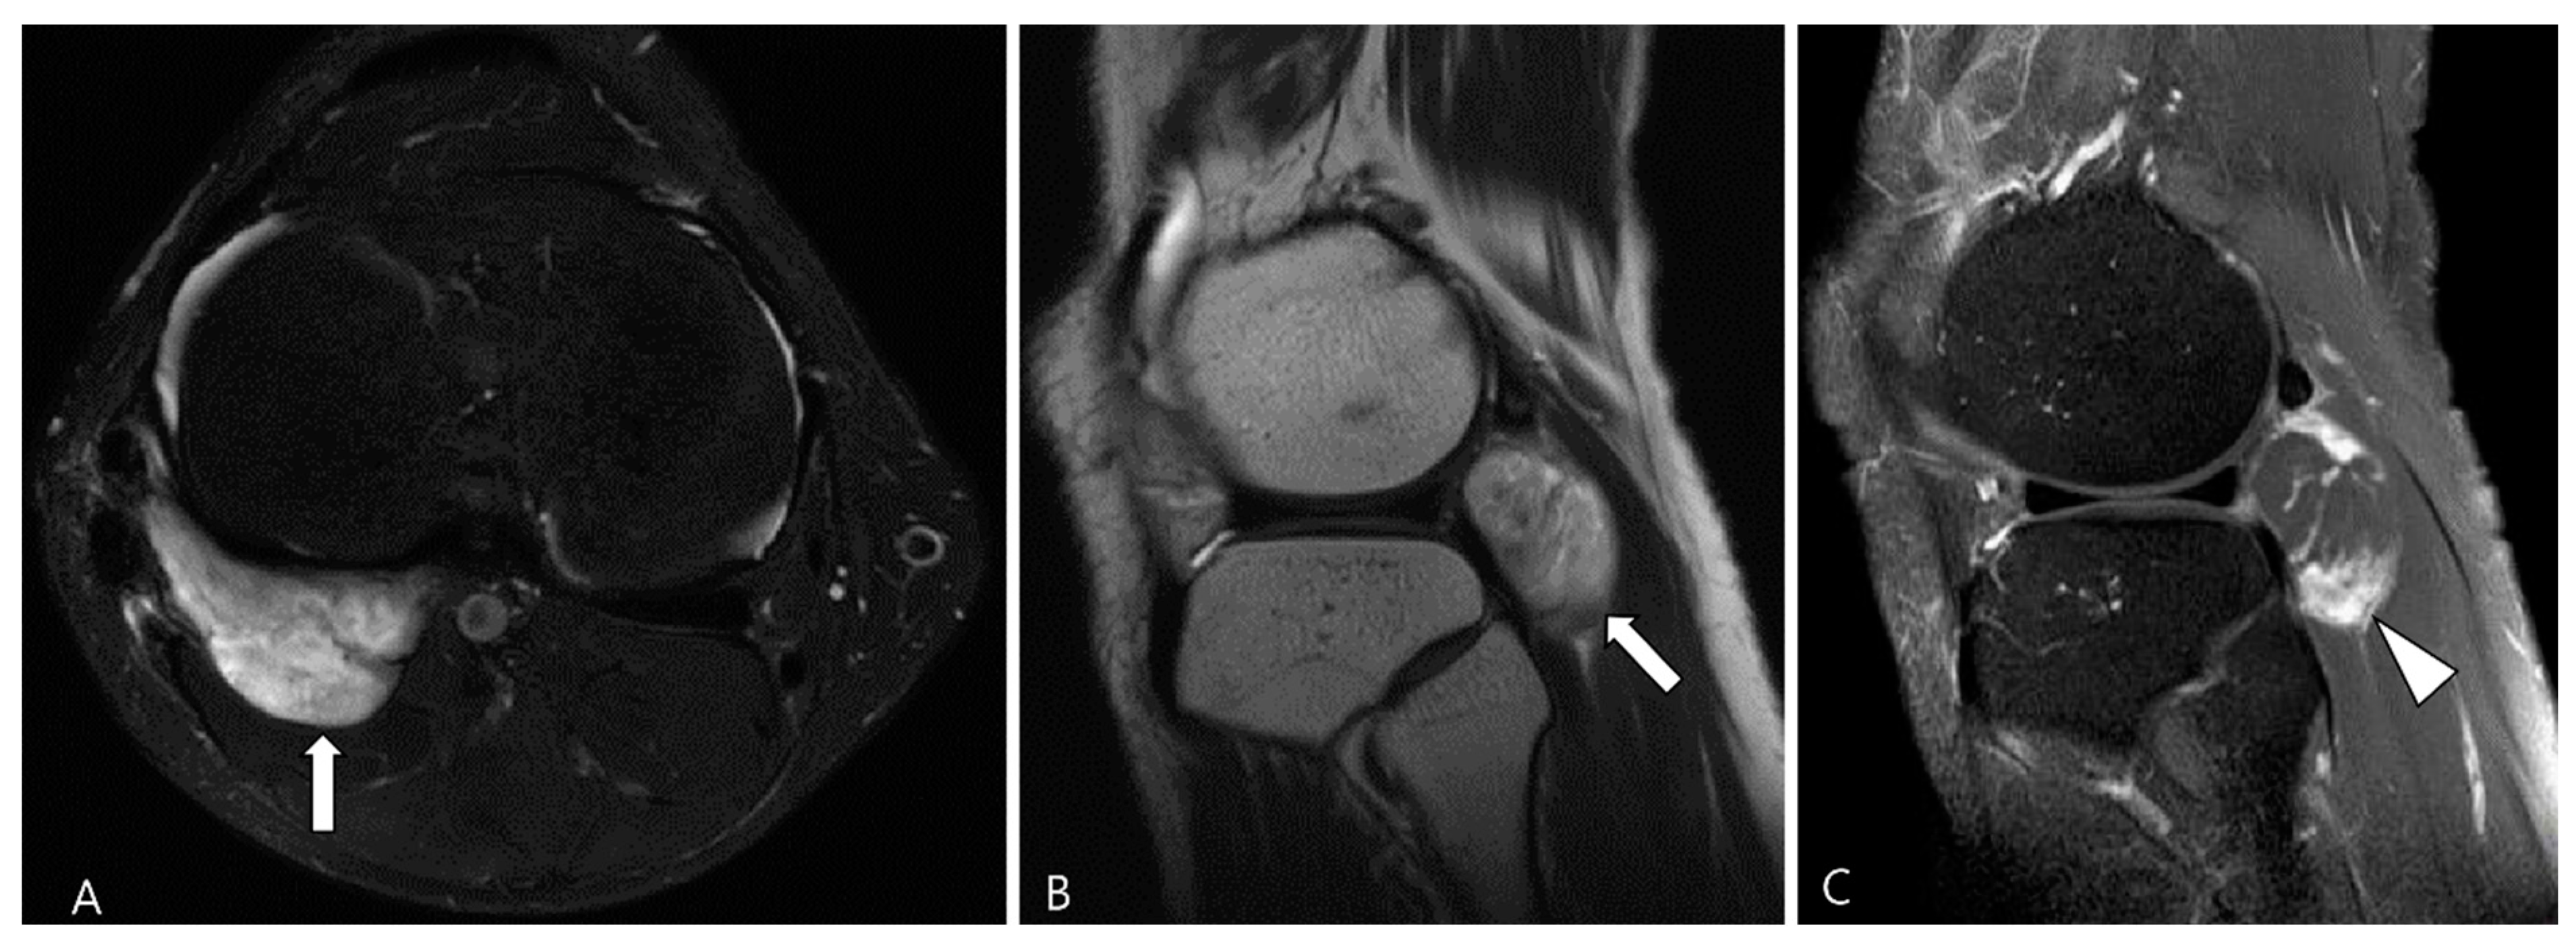

2.3. Morphological Findings for D-TSGCT

2.4. Relationship to Adjacent Structures of D-TSGCT

3.1. Differential Diagnoses of Intra-Articular D-TSGCT

3.1.2. Synovial Chondromatosis